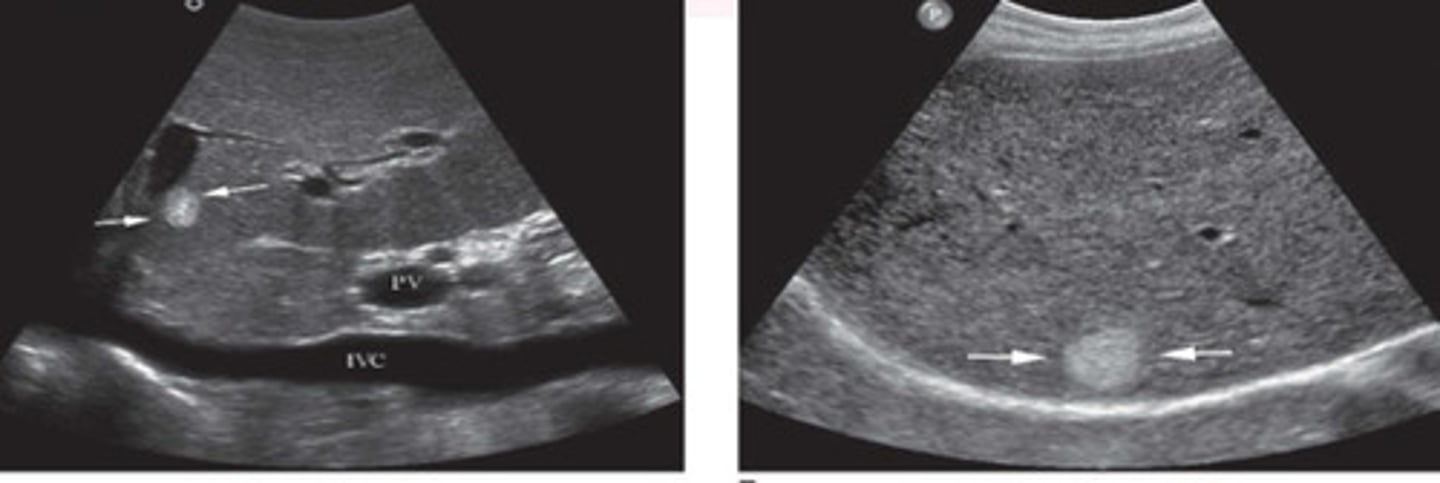

Hemangioma

What does this image show

Hemangioma (would need follow up bc bigger)

Atypical appearance of hemangioma